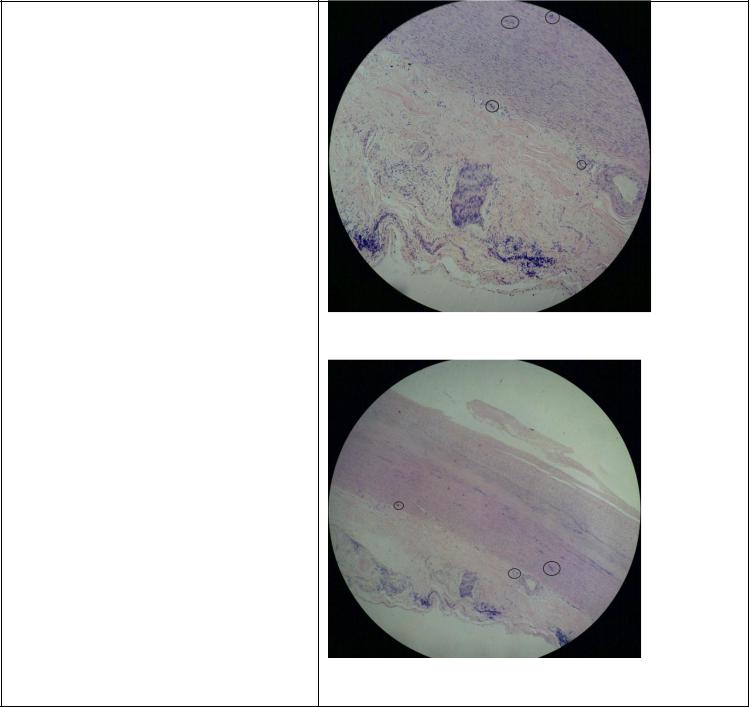

14. Сифилитический мезаортит

Специфическая гранулема-гумма

развивается в третичном периоде сифилиса

При микроскопическом исследовании обнаруживается воспалительныйпроцесс,

начинающийся со стороны vasa vasorum адвентиции и распространяющийся на среднююоболочку. Здесь имеются скопления лимфоидных, плазматических клеток, фибробластов, гигантских клеток типа Пирогова — Лангханса, иногда мелкие очажки некроза.

Этот процессобозначается как сифилитический мезаортит. Воспалительный

инфильтрат разрушает эластические волокна среднейоболочки и по мере созревания клеток в медииостаются поля соединительнойткани с обрывками

эластических волокон(1). В результате этого процесса прочность стенки аорты уменьшается, просвет ее расширяется и образуется аневризма.

Окраска на эластику

Выделены сифилитические гранулемы

Гематоксилин-эозин